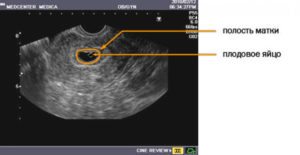

Описание плодного яйца

Плодное яйцо — это защитные оболочки, окружающие зародыш. Они прикрепляются к стенке матки, образуя с ней сосудистую связь. Через сосуды растущий зародыш получает питание из материнской крови. Плодное яйцо на УЗИ выглядит, как округлое образование темно-серого цвета.

Оно становится видным, когда достигает размера 5 мм. Это соответствует 4 неделям беременности. Эмбрион внутри яйца пока не виден. Его можно рассмотреть после 35-го дня, выглядит он как темная полоска. Части его тела можно увидеть на 12 неделе беременности — в этот срок обычно и проводят первое обследование.

- Трансвагинальное УЗИ – основной метод диагностики. При этом выявляются следующие эхо-признаки:

- отсутствие эмбриона в полости матки;

- матка имеет вид песочных часов;

- тело матки увеличено вширь, цервикальный канал расширен;

- плодное яйцо определяется в просвете канала шейки матки ниже уровня расположения внутреннего зева;